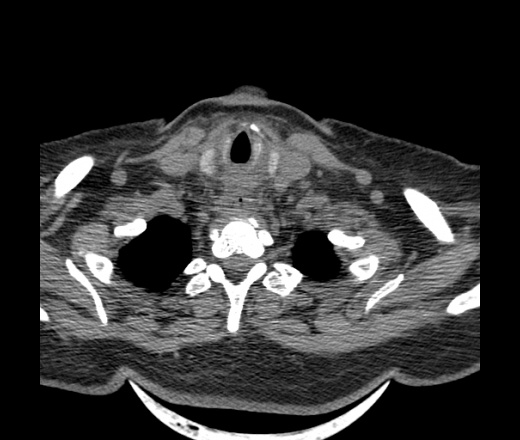

Женщина поступила в х/о спустя 4 дня после того как при употреблении карася подавилась костью.

Наличие газа в средостении на протяжении тел С2-С6 (медиастинальна эмфизема); рыбная кость на уровне тела С6.

При всем уважении, но говорить о медиастинальной эмфиземе, оценивая мягкие ткани шеи, как-то слишком резко. На мой взгляд, это ретрофарингеальное пространство.

Эвакуировали почти 100мл гноя. Но кость не смогли найти. Думаю что она даст дальнейшее ослоднение. Эндоскопически за черпалонадгортаной звязкой не смогли зайти в пищевод, все мягкие ткани отечные, просвет пищевода сдавлен. По всей видимости параэзофагеальная клетчака тоже задействована. Эмпиема, если ее можно так назвать, незнаю как правильно дошла до уровня яремной вырезки. Чем закончиться напишу. Ждем медиастинита.

Флегмона заглоточного пространства шеи, только операция, флегмоны вскрывают. Риск медиастинита.

Согласен с Вами; конечно, наличие газа в клетчатке ретрофарингеального пространства (затмение с опечаткой..). К сожалению, процесс "продвигается" к медиастиниту. Но почему никто, не отмечает наличие рыб. кости; или это для Всех очевидно?

Кость то мы сразу выявили, размеры где то 17*2мм, но ее так и не получается найти в этой каше